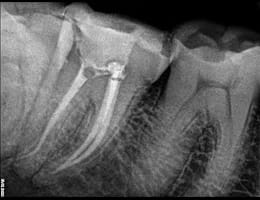

The dentist examines the tooth and takes X-rays to confirm the extent of infection or damage.

DIGITAL X RAY “RVG”

We invest in the latest imaging technologies like Carestream RVG IOPA to provide superior diagnostic capabilities.

Expert Analysis:

Our experienced dental team is skilled in interpreting RVG IOPA images, ensuring that any dental issues are accurately identified and addressed.